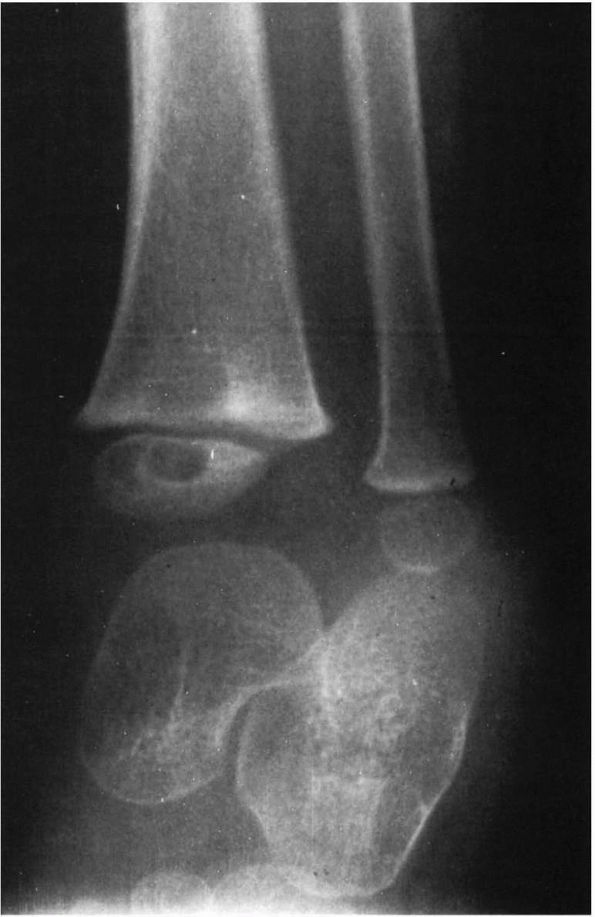

FIGURE 5-9.

Oblique radiograph of the distal tibia of an 11-year-old girl with a 1-month history of pain, swelling, and redness of the ankle. A metaphyseal lesion of the distal tibia resembles subacute osteomyelitis; however, the biopsy revealed that the lesion was an osteogenic sarcoma. |

epiphysis, can usually be diagnosed as subacute osteomyelitis

radiographically; however, in some instances the diagnosis is in

question. When the diagnosis is not clear radiographically, open biopsy

is required in making the diagnosis (Figure 5-9).

In addition, because there is a radiographic lesion, an abscess has

formed and debridement is usually required, although some authors have

reported healing without debridement. Frequently no pus is evident at

exploration; however, one may find granulation tissue within the cavity

that should be debrided. Cultures may be sterile, but Staphylococcus aureus and Staphylococcus epidermidis

are the most common organisms. Some have suggested that debriding these

lesions is not required. These lesions will heal with adequate

antibiotic treatment. It has been recommended that patients be treated

with antibiotics for at least 4 weeks or until significant healing is

seen radiographically (Cole 1982; Ezra et al. 2002).

Therefore, if one is comfortable with the radiographic diagnosis of

subacute osteomyelitis, then antibiotic treatment alone without biopsy

is appropriate. If there is inadequate response, as judged by the

clinical course and radiographic healing, then biopsy is required.